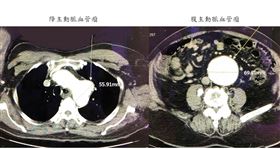

背痛到昏倒急送醫 「不定時炸彈」藏體內

造成血管瘤發生的原因,最常見的就是長期的高血壓,讓血...